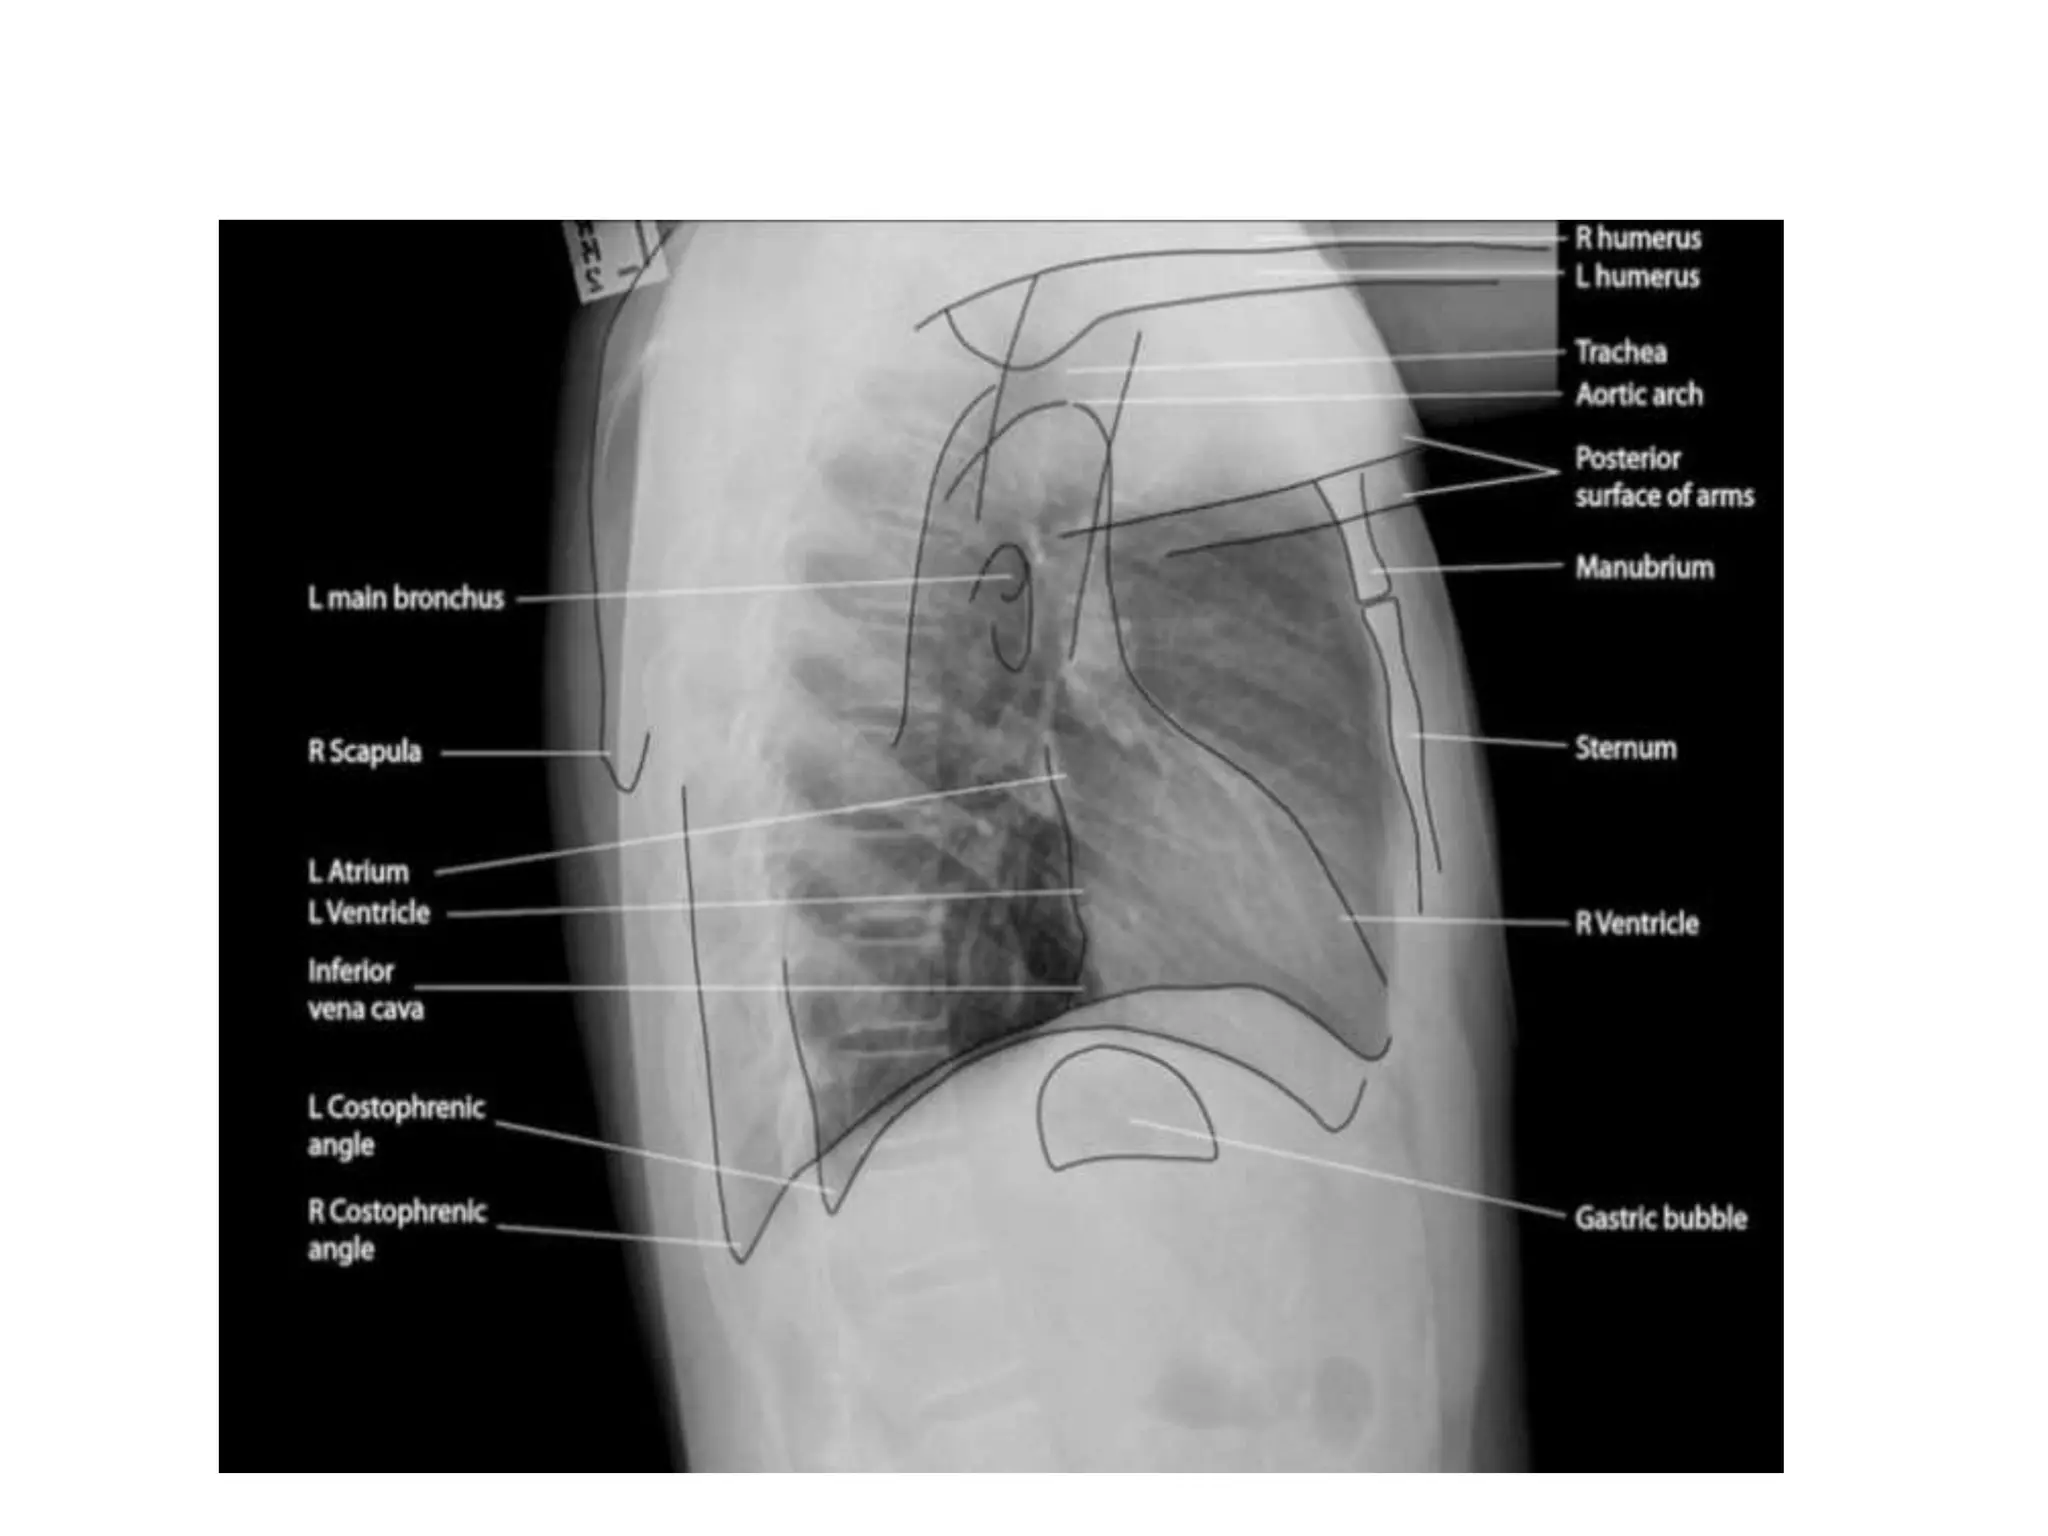

• A systematic approach for viewing chest X-rays ensures no

important structures are ignored

• Anatomical structures to check

1. Trachea and bronchi

2. Hilar structures

3. Mediastinum

4. Heart

5. Lung zones

6. Lung lobes and fissures

7. Pleura

8. Costophrenic angles

9. Diaphragm

10.Soft tissues

11.Bones